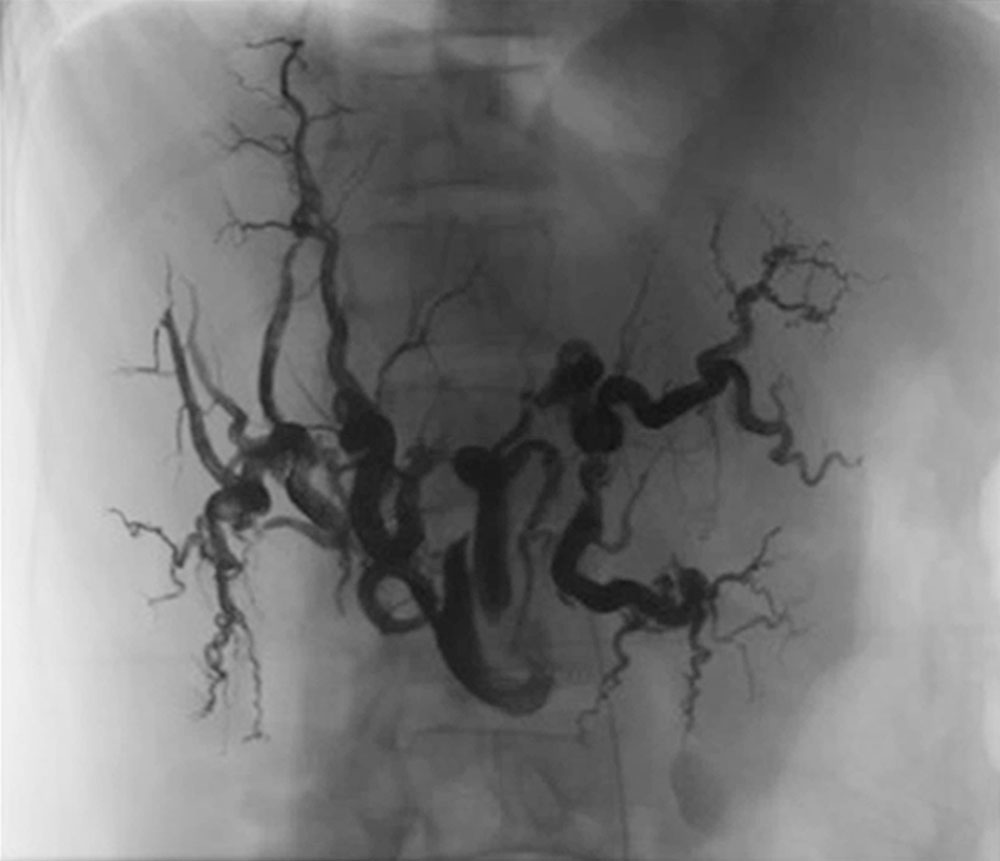

Die prognostisch ungünstigsten Gefäßanomalien bei Patienten mit Morbus Osler entwicklen sich jedoch im Laufe des Lebens aus zunehmenden arteriovenösen Malformationen der Leber, die massive Ausmaße annehmen können und ebenfalls zu einer Rechtsherzbelastung bis zum Versagen führen können. Die früher dann häufiger versuchte Lebertransplantation wird heute meistens durch eine etappenweise durchgeführte selektive, segmentweise Embolisation der Leber-AVM vermieden.